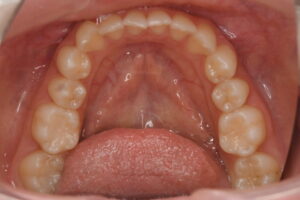

▼初診時の口腔内写真1

▼初診時の口腔内写真2